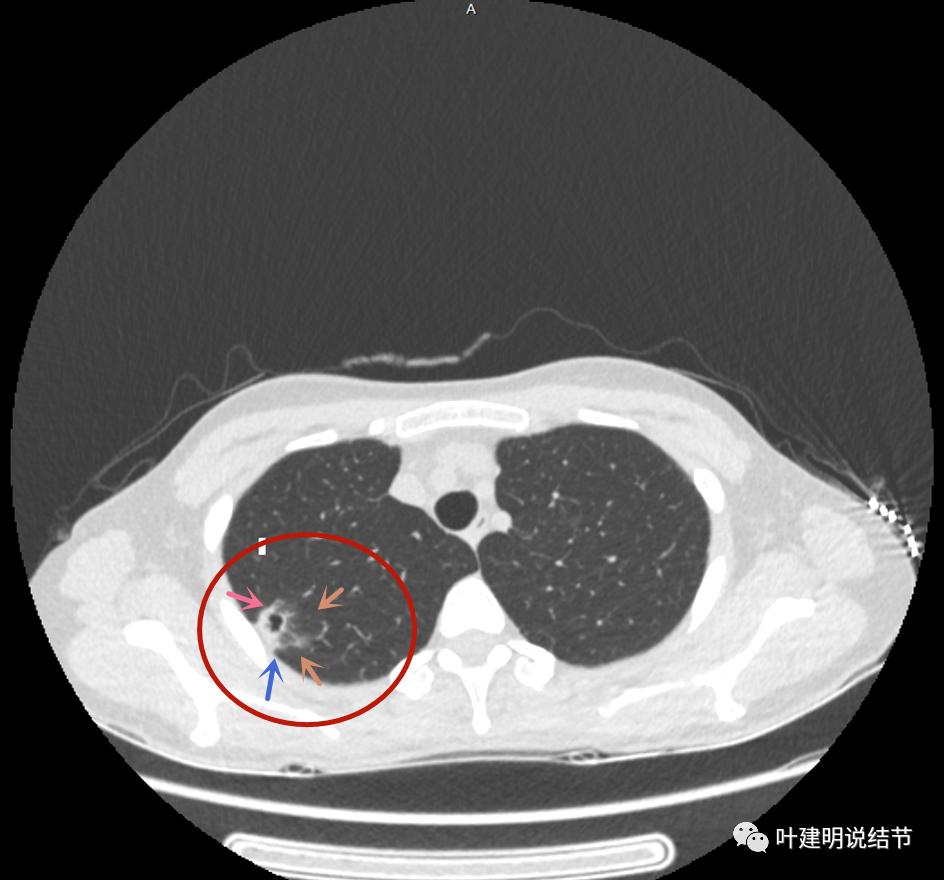

我们再来看薄层的CT图像:

病灶出现,模糊的磨玻璃影

部分密度过高,且呈条状

邻近胸膜有增厚(蓝色箭头),主病灶边界较清(红色箭头),实性部分密度过高(粉色箭头),旁边有磨玻璃影,散且模糊(砖色箭头)

邻近胸膜有增厚(蓝色箭头),主病灶实性部分密度过高(粉色箭头),旁边有磨玻璃影,散且模糊(砖色箭头)

邻近胸膜有增厚(蓝色箭头),主病灶实性部分密度过高(粉色箭头),旁边有磨玻璃影,散且模糊(砖色箭头),病灶有空腔(黄色箭头)

主病灶边界较清(红色箭头),实性部分密度过高(粉色箭头),病灶边缘向内凹,缺乏膨胀性(桔色箭头),病灶有空腔(黄色箭头)

邻近胸膜有增厚(蓝色箭头),主病灶的壁密度过高且整个壁密度都高(粉色箭头),旁边有磨玻璃影,散且模糊(砖色箭头)。内壁不均质(此不舒服)

邻近胸膜有增厚(蓝色箭头),主病灶囊壁密度过高(粉色箭头),内部有突起(细红色箭头),旁边有磨玻璃影,散且模糊(砖色箭头),中间有空腔,内壁有些区域又是光滑的

邻近有卫星灶(绿色箭头),主病灶密度过高(粉色箭头),旁边有磨玻璃影,散且模糊(砖色箭头)

邻近胸膜有增厚(蓝色箭头),主病灶边缘较为平直,缺乏膨胀性(桔色箭头),实性部分密度过高(粉色箭头),旁边有磨玻璃影,散且模糊(砖色箭头)

病灶边缘较为平直,膨胀性不足(桔色箭头)